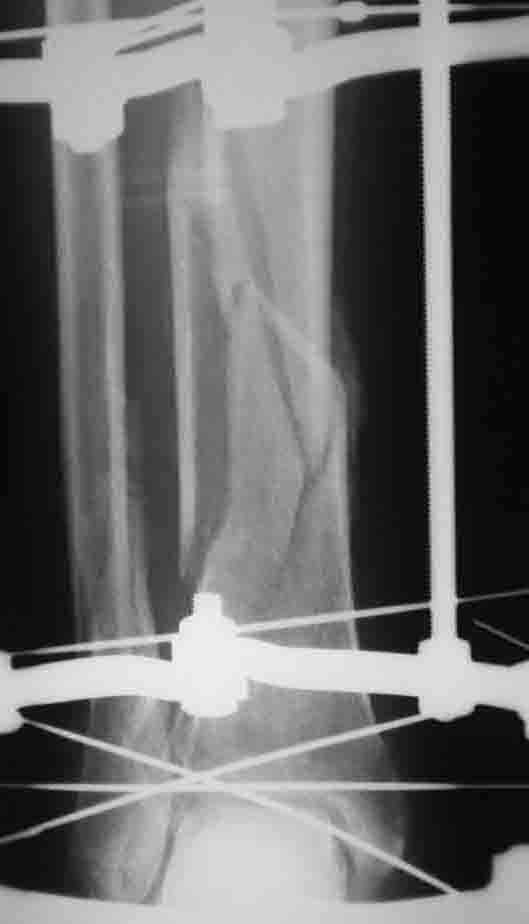

вот при таком внутрисуставном переломе ВЧКО по Илизарову будет методом выбора во многих (возможно, в большинстве) британских центров, где этой методой владеют.

Ну, при таком-то переломе и накостный остеосинтез возможен, и даже интрамедуллярный. Аппаратная фиксация становится предпочтительной, наверно, все-таки при более многооскольчатых переломах собственно суставной поверхности, когда спицы в силу их меньшего диаметра позволяют фиксировать множественные мелкие фрагменты под любыми углами.

Алекс, снимок сильно ужат и сфотографирован мыльницой, потому я и написал отдельно, что он внутрисуставной.

Пластиной. конечно, можно, но будет травматичнее и ничем не прочнее, чем аппаратом.